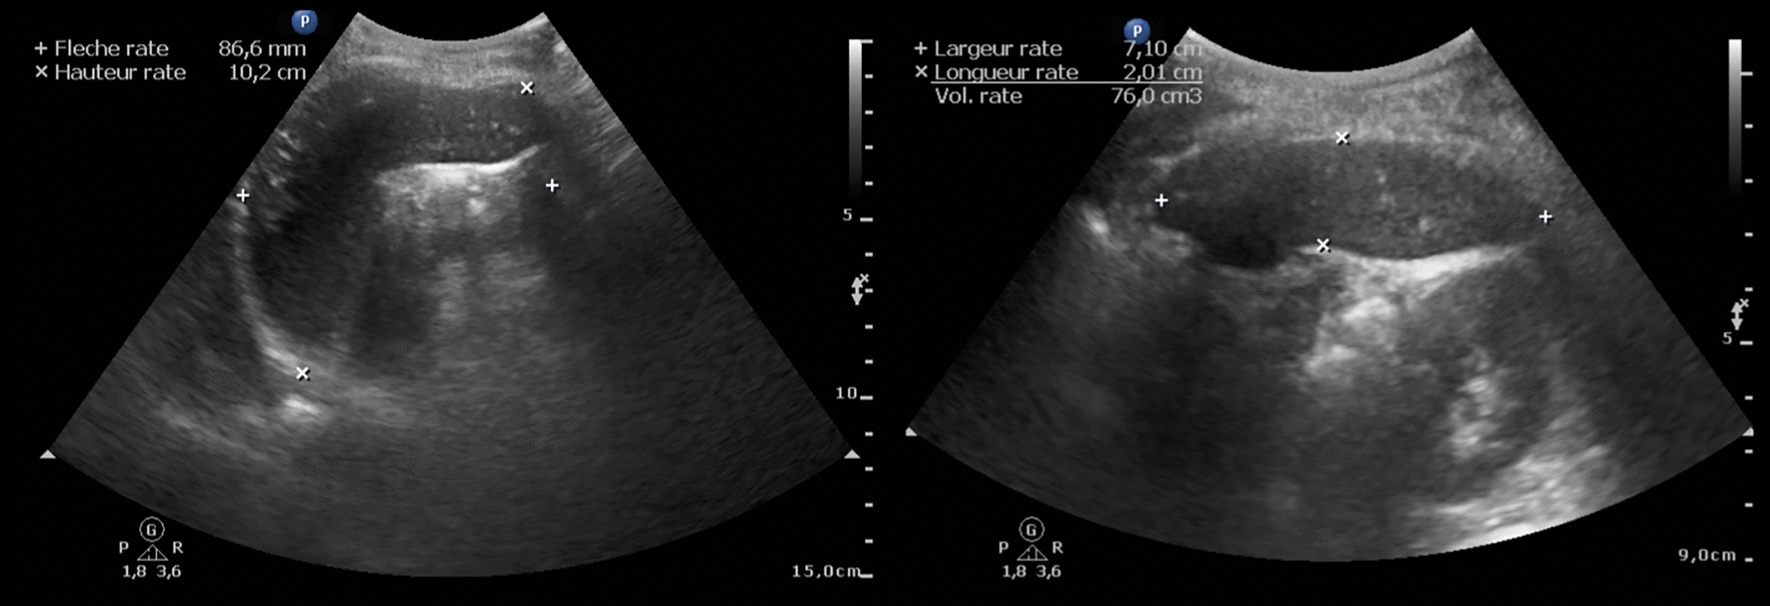

Methods: We included 981 participants aged 18-88 years in a cross-sectional study conducted in May-June 2022 in the Republic of the Congo. Centralized ultrasonographic examination was performed. The primary outcomes included SV, splenomegaly (cranio-caudal-distance ≥ 13 cm), and anatomical hyposplenia (AH) (SV ≤ 80, ≤ 110 or ≤ 150 cm3). Blood samples were analyzed for L. loa MFD, Plasmodium-PCR, Anti-Plasmodium falciparum-IgG, total IgM, sickle-cell disease status, and hematological abnormalities. Linear and logistic regressions were used to assess these associations.

Results: Among 981 participants, 139 (14.1%) had splenomegaly, and 26 (2.7%) and 175 (17.8%) had SV ≤ 80 and ≤ 150 cm3, respectively. L. loa microfilariae were detected in 353 (35.6%) participants. A gradient effect was observed in each model, with the highest MFD (> 30,000 mf/ml) having the highest adjusted odds ratio of 17.94 (95% CI: 2.91-110.76, P = 0.002), 5.94 (95% CI: 1.40-25.17, P = 0.016), and 5.77 (95% CI: 1.95-17.12, P = 0.002) for SV ≤ 80, 110, and 150 cm3, respectively. Anti-P. falciparum-IgG levels were gradually associated with splenomegaly. Fourteen participants met the criterion for hyper-reactive malarial splenomegaly (HMS). Conversely, higher L. loa MFD was correlated with AH, with an attributable fraction of 25%, and the presence of splenic parenchymal lesions.